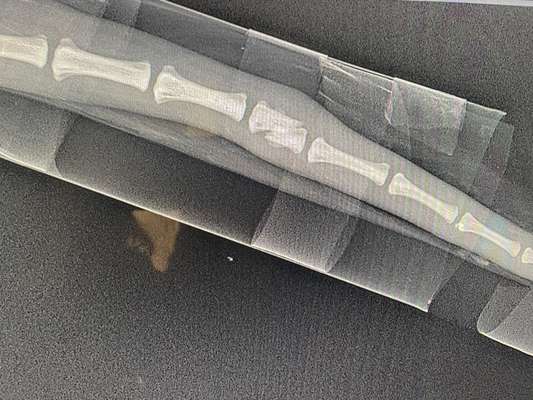

Vermutlich haben die TA eine Amputation empfohlen, weil die Fraktur verschoben ist und die Bruchränder scharf erscheinen.

Bei so verschobenen Brüchen besteht die Gefahr auf ein unechtes Gelenk,

d.h. es besteht eine erhöhte Verletzungsgefahr, weil die Rute dann instabil ist.

Nach 6 Wochen verheilt es schon ganz gut. Weitere 4 Wochen Schiene tragen ist aber notwendig